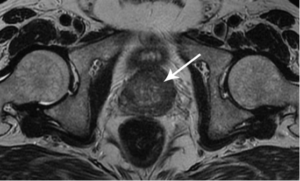

Voglio mostrarvi alcune immagini, in modo che possiate vedere da voi cosa succede al tratto urogenitale e agli altri organi di un uomo che non fa sesso.

Ecco come appare l’infiammazione prostata causata dal ristagno di spermatozoi (quando i testicoli non vengono svuotati). L’infiammazione persistente porta dapprima all’adenoma prostatico, e successivamente al tumore alla prostata (in base alle statistiche, il 38% degli uomini muore per questo motivo). In mancanza di sesso, questo succede sempre ed è per questo che l’adenoma prostatico viene chiamato “la malattia degli anziani”.